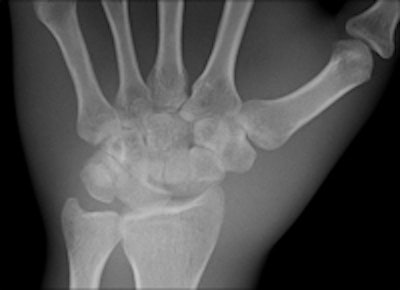

Two images of a hand phantom obtained using different equipment: Fuji's CR system and DRX-1 from Carestream. All images courtesy of Dr. Thomas Lehnert.

A third image of a hand phantom obtained using DR9500 from Carestream.Identical in size to a standard CR cassette, the detector can be inserted into an existing wall stand or table Bucky and used in combination with existing x-ray generators from a number of original equipment manufacturers, presenting an attractive option for modest-budget facilities. The flexibility of the portable detector provides great advantages in time-critical environments where an x-ray image can now be captured and viewed in less than six seconds, he explained.